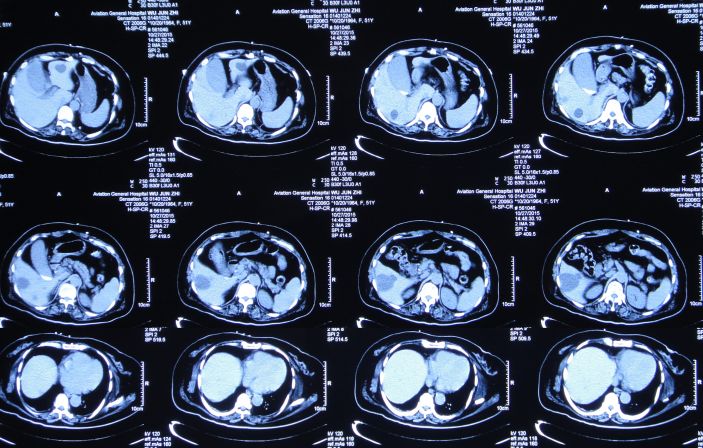

入院后第一天即2014年12月15日,患者神清,出现左眼肿胀,视力消失,左眼瞳孔增大,对光反射消失,左侧外耳道见澄清液体溢出,复查头CT:左额叶脑挫伤较前加重(图3)。

图3:2014年12月15日头CT:左额叶脑挫伤较前加重